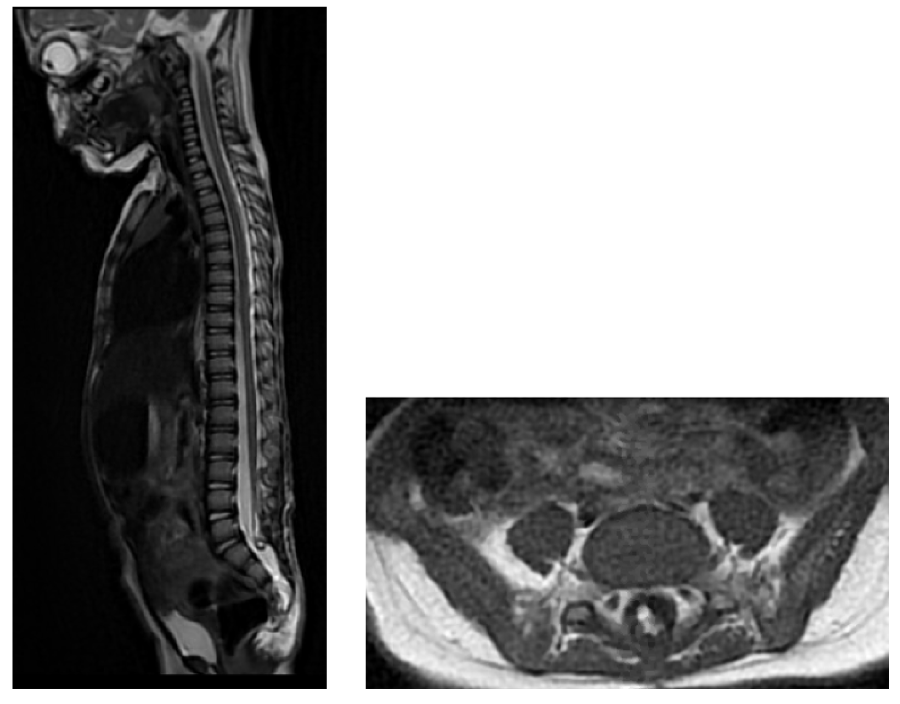

At 1 year and 4 months old, she was admitted to the emergency department for sub-acute loss of walking which had started a month earlier. She also exhibited sudden onset of urinary retention. She was thus transferred to our specialised center for management. Upon arrival, she was moving spontaneously on all-fours. She was able to stand up with support and could walk couple of steps but only with assistance. She had dorsiflexion and eversion weakness on the left greater than the right side with manual muscle testing being under 3/5. She did not respond to tactile stimulation on the left lower limb. Due to the sudden neurological deterioration cerebral and spinal MRI were ordered. The cerebral MRI was normal, and the spinal MRI was remarkable for the appearance of a large syringomyelic cavity extending from T11 to S1 with associated spinal cord edema (figure 1). She thus underwent a detethering surgery with restoration of perimedullary CSF space and near total lipoma resection. At day 1 post-surgery she had complete recovery of motor and sensory functions. Bowel and bladder resumed normal functions at day 2 post-surgery.

Figure 1: Initial radiological presentation at 7 months of age of an anterolateral trans dural transitional conus lipoma A: Sagittal T2 B: Axial T1 View Figure 1